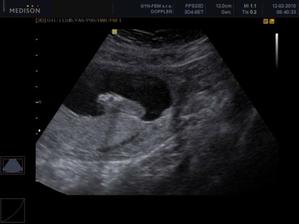

30.12. Jsem se byla zaregistrovat k porodu u Apolináře. ROK 2010 🙂 TO SE BUDOU DÍT VĚCI. 12.1. interní vyšetření + EKG a odběr - všechno OK, 14.1. UTZ žil kvůli natékání nohou (už ráno mám kotníky jako bambule). Výsledek: tromboza nehrozí UF!, nedomýkavost chlopní tepen, pže tělo je víc zatíženo. Doporučeno: nosit těhu punčochy, hodně pít, víc chodit, málo sedět a stát. Pak jsem utíkala na gyn na triplle testy a sestra mě objednala i na velký UTZ kam půjde i manža a budeme mimíska mít na DVD. Jsme oba natěšený! 20.1. UTZ ledvin - vše v pořádku. Tak velký UTZ proběhl OK. Nechceme vědět co to bude tak to stále nevíme 🙂)) . Triplletesty jsou taky v pořádku. 18.2. poradna - tak jsem měla nízký tlak 🙂)) jindy ho mám vysoký tak jsou trošku zmatený. Říkám, že mají blbý tlakoměr. Gynekologicky a miminkovsky všechno dobrý. 21.2. domluveno jméno pro klučíka - TOMÁŠEK .... ještě tu holčičku 😉)).